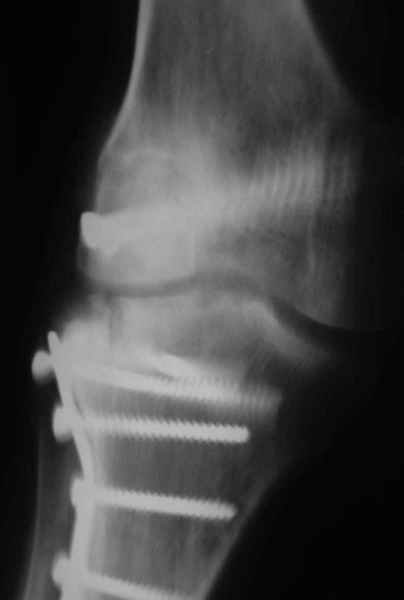

Уважаемые коллеги!На прием обратилась больная 38 лет. Травма 17.01.2005. 23.01.2005 - операция в одном из стационаров области - остеосинтез мыщелка бедра винтами, Остосинтез мыщелка большеберцовой кости L-образной пластиной.

Остальные снимки Ноябрь 2005

Иммобилизация лонгетной гипсовой повязкой 2 мес. После прекращения иммобилизации, пр начале ЛФК отмечена нарастающая вальгусная деформация конечности. Рентгенограммы в приложении. Хотелось бы узнать Ваши предложения по тактике лечения

Уважаемый Евгений ! Спасибо за ответ, но мне представляется, что в нашем случае основной проблемой является не столько прогрессирующий вальгус конечности, сколько несросшийся перелом мыщелка бедра и дефект мыщелка большеберцой кости - вероятно первичная репозиция выполнялась без пластики.

На своем горьком опыте убедился, что синтезировать мыщелковые импрессионные внутрисуставные переломы б\б кости без костной пластики - дело неблагодарное, рецидивируе деформация, мыщелок всегда *проваливается*. Чистые split type переломы можно ограничиваться и одной только межфрагментарной компрессией.